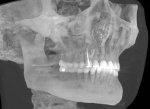

image.png

Че за бородавка костная нахуй? Ты че ваще нахуй?

>>331338306

Сам в ахуе, тупа дырки сквозные. Может там нервы проходят?